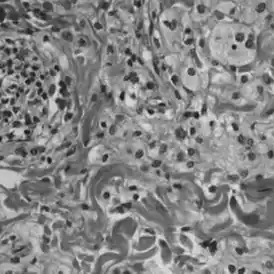

Для постановки диагноза ЭЧБ требуется проведение гистологических исследований. К типичным гистологическим признакам ЭЧБ относятся локализованные вдоль участков фиброза полиморфные ксантогранулемы, состоящие из CD68+, CD1a-, S100- пенистых гистиоцитов. При лангергансоклеточном гистиоцитозе, представлены гистиоциты классов CD68+, CD1a+.